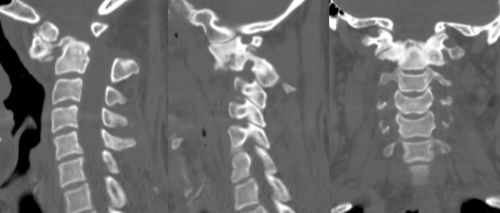

图片

患者术前部分影像